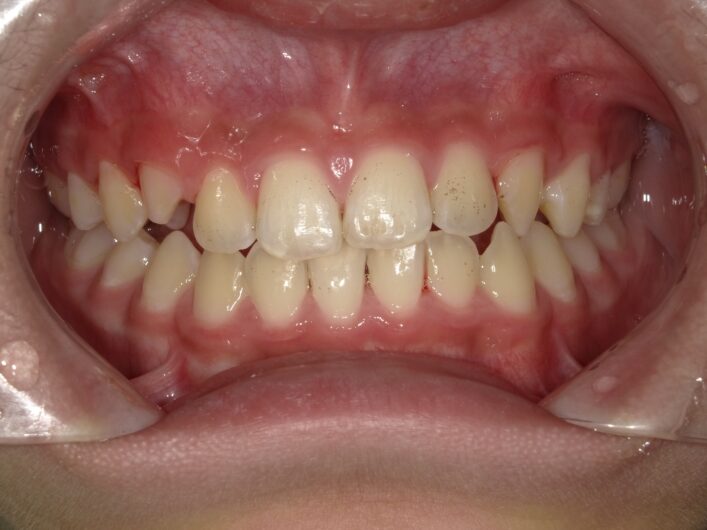

【症例】混合歯列期の反対咬合(8歳・男児)

混合歯列期に上顎の発達不足が見られ、反対咬合を呈していたため、治療介入。

上顎の成長を促すことで、骨格性の反対咬合への進行を防ぐことができました。

■ 初診時の状態

この時期はすでに上下の1番・2番・6番が萌出しており、

顎の成長コントロールが可能な重要なタイミングでした。

反対咬合を放置すると、

・ 上顎の成長が抑制される

・ 下顎が前方に成長しやすくなる

・ 将来的に骨格性の受け口へ進行する可能性

があるため、早期の1期治療を開始しました。

■ 治療の考え方

本症例では、

「歯を動かす」のではなく、

「上顎の発達を促す」ことを目的としました。

混合歯列期はまだ骨が柔らかく、

適切なタイミングで介入することで顎の幅や前方成長をコントロールできます。

装置による上顎の拡大と、

咬合誘導を行いながら経過を観察しました。